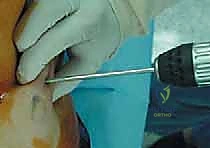

3. نحت وتشكيل رأس عظمة الفخذ

بدلاً من قطع الرأس، يستخدم الجراح أدوات ميكروسكوبية ومثاقب دقيقة جداً لإزالة الغضروف التالف وطبقة رقيقة من العظم المريض، ليتم "نحت" رأس العظمة ليصبح جاهزاً لاستقبال الغطاء المعدني بشكل مثالي.

4. تركيب الغطاء المعدني (Femoral Component)

يتم تثبيت التاج أو الغطاء المعدني الأملس فوق رأس عظمة الفخذ المنحوت، وغالباً ما يتم تثبيته باستخدام مادة أسمنتية طبية خاصة لضمان ثباته المطلق.